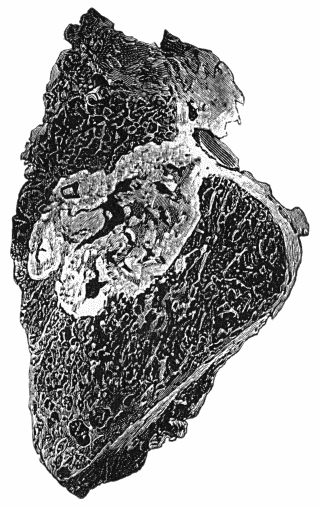

| 114. | Section through Gouty Bursa | 428 |